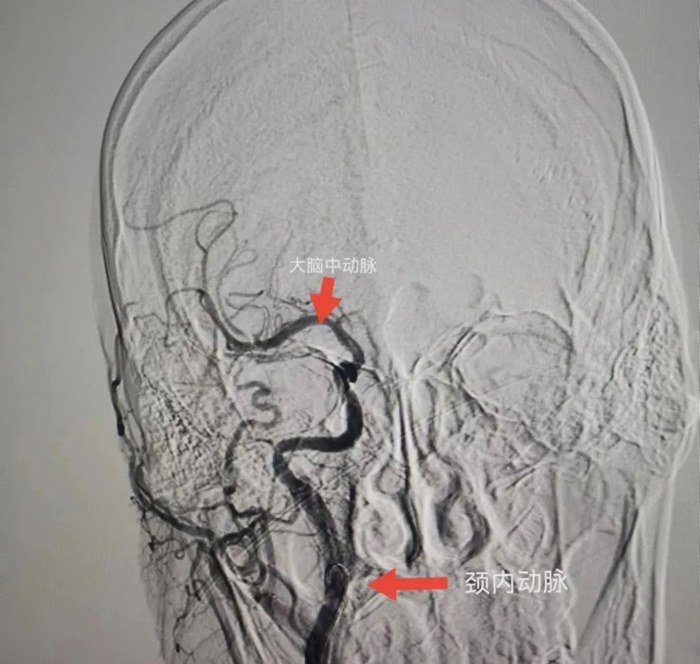

與患者女兒溝通,征得患者女兒同意后,立刻聯系CT室,半小時內完成CT檢查,證實患者右側頸內動脈和右側大腦中動脈閉塞,存在70毫升的缺血腦組織,有取栓適應癥。再次和患者女兒溝通,患者女兒接受風險簽字手術。立刻聯系介入室和麻醉科,一個半小時完成手術。

術中給予患者右側頸內動脈植入支架和右側大腦中動脈取栓,患者血管達到3級再通。術后第二天,患者神志轉清醒,左下肢可抬起。術后第5天,患者左側肢體均可活動達到4級肌力,左手可持物,能獨立行走。

患者腦CTA結果